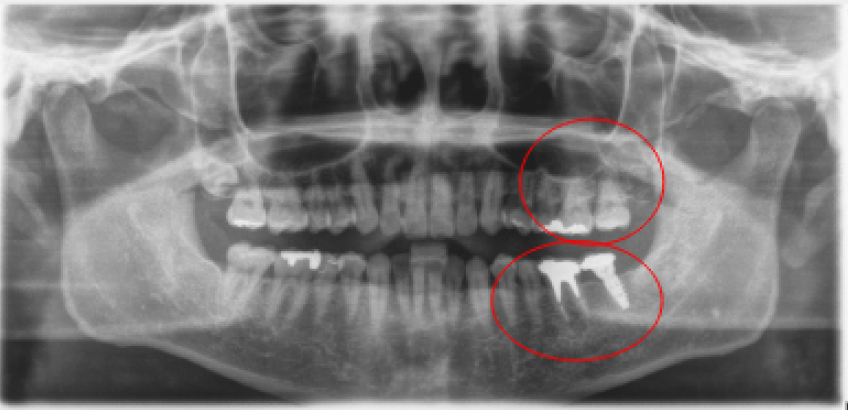

治療前治療後

| 治療内容 | インプラント奥歯1本・根管治療6歯 |

|---|---|

| 患者様の年齢 | 54歳 |

| 患者様の性別 | 女性 |

| 治療期間 | 2年 |

| 治療回数 | 根管治療合わせて70回程度 |

| 治療費用 | インプラント1歯 50万円/根管治療6歯 30万円 |

| 治療で得られるメリット |

|

| 治療する際に起こる リスク・副作用 |